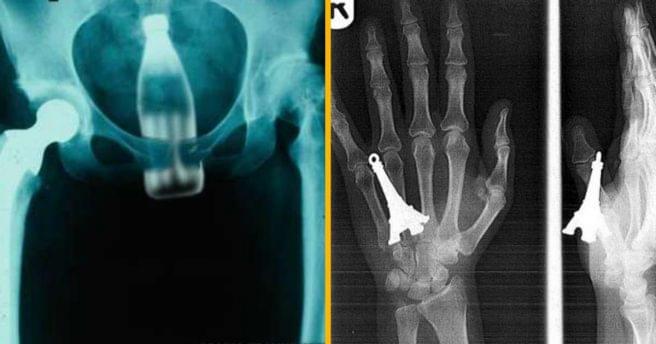

Vous êtes seul, chez vous, un vendredi soir, tout déprimé, à écouter Damien Saez en boucle (pourquoi vous faites ça). Puis vient la chanson « Sexe » qui vous émoustille, mais votre canard vibrant étant tombé en panne, vous décidez de vous acoquiner avec la télécommande (ou l’ampoule du salon, c’est au choix). Manque de […]